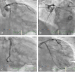

Abbildung 4a-d: Angiographie (a-c) Diagnostische Angiographie; (d): nach CX-Intervention |

Abbildung 4a-d: Angiographie

(a-c) Diagnostische Angiographie; (d): nach CX-Intervention |